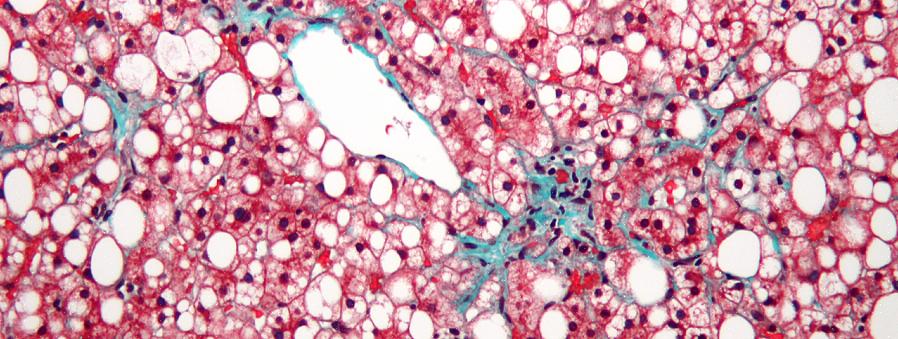

צלקות יכולות להופיע לאחר ניתוח, חתכים, טראומות או כוויות. התהליך שעובר העור כדי לרפא את הפצעים הללו הוא כנראה מורכב יותר ממה שאתה חושב. ראשית, הדימום נושא אלמנטים כמו טסיות דם, גליקופרוטאין או פיברין ומנסה לכיווץ את כלי הדם שלך.

מאותו רגע, הגוף פועל ללא לאות כדי לרפא את הפצע הזה. מעל לכל, הגוף שלך מנסה למנוע מחיידקים להיכנס. השלב האחרון של הריפוי ידוע גם בשם שיפוץ ויכול לקחת ימים, שבועות או אפילו חודשים. הכל תלוי בגודל ובמאפייני הפצע.

אם הדרמיס והפאשיה (השכבה הפנימית של העור, עם קולטני כאב) מושפעים מפציעות עמוקות יותר וצלקות, זה יכול לשנות את המבנים העדינים שלהם. כתוצאה מכך, זה יכול להוביל פחות אינטראקציה פנימית-חיצונית.

סיבי Fascia הם פחות אלסטיים במהלך תהליך הריפוי. לחץ ומתח הם הבעיות העיקריות כאשר אתה מנסה להתאמן, להרים חפץ או להשתמש בכוח רב.